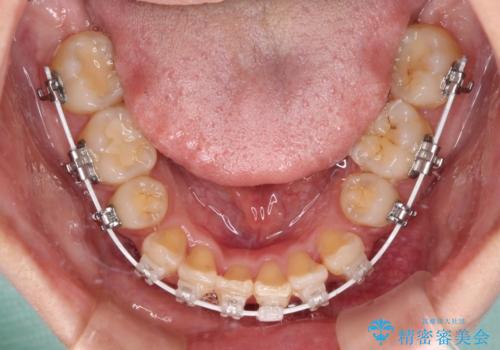

後戻りにリカバリーに少し時間を要しましたが、1年強の期間で無事に治療を終えることができました。